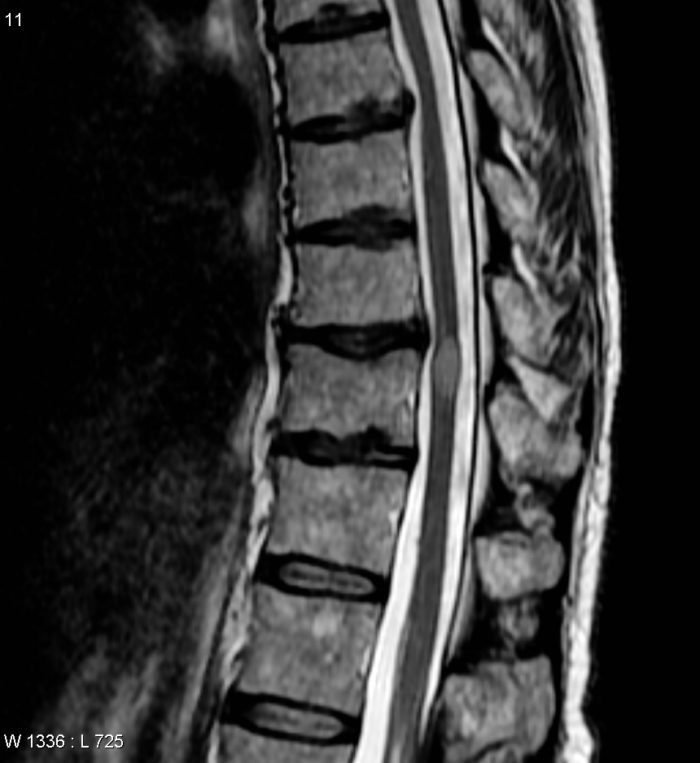

Arthritis In Entire Spine. osteoarthritis of the spine is a breakdown of the cartilage of the joints and discs in the neck and lower back. It can occur anywhere along the spine. osteoarthritis of the spine specifically affects the facet joints, which are the bones that connect the spine, as well as the ligaments and cartilage between the spinal bones that make up. Usually the low back and. spinal arthritis causes symptoms like pain, stiffness and inflammation in the joints between the vertebrae in your spine. spinal arthritis is inflammation of the facet joints in the spine or sacroiliac joints between the spine and the pelvis. ankylosing spondylitis, also known as axial spondyloarthritis, is an inflammatory disease that, over time, can cause some of the bones in the spine,. It can be scary to find out a. spinal osteoarthritis (oa) is a chronic degenerative disease of the spine that involves wear and tear of the spinal joints. osteoarthritis (oa) is the most common form of arthritis that affects the back.